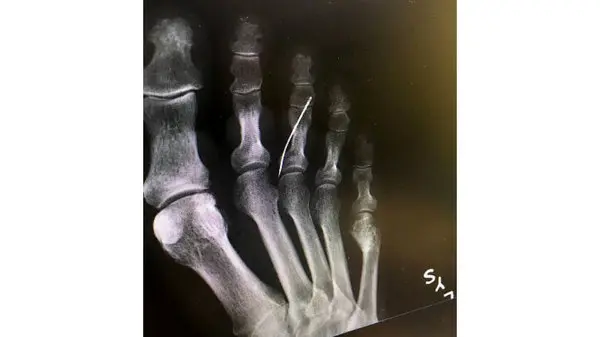

پیرزنی به طور بسیار باورنکردنی و عجیب از رفتن سوزن خیاطی به داخل پای خودش اطلاع نداشت.مادربزرگی که نامش منتشر نشده است هنگام عبور از اشعه ایکس متوجه واقعیتی شد که باور کردنی نبود او سوزن خیاطی در پایش داشت که هیچ توجیهی برای آن نداشت .

این زن به دلیل مرض دیابت Diabetes حس را در پایش از دست داده است و از وجود سوزنی که در پایش بوده هیچ اطلاعی نداشته. نوه ی او که اهل کالیفرنیا بود تصاویر او را به اشتراک گذاشت کاربران زیادی نظرات متفاوتی داشتند اما او وقتی به پزشک Doctor مراجعه کرد سریع او را به طور اورژانسی عمل کرده و سوزن را بیرون آوردن عفونت پای او به حدی بود که باید در بیمارستان می ماند و حالا هیچ معلوم نیست چقدر طول بکشد تا پوستش التیام پیدا کند.